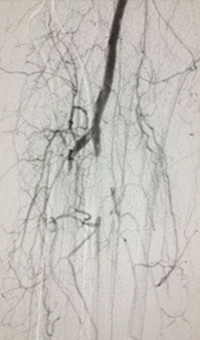

xray of femoral vein pre-treatment.

Femoral vein pre-treatment